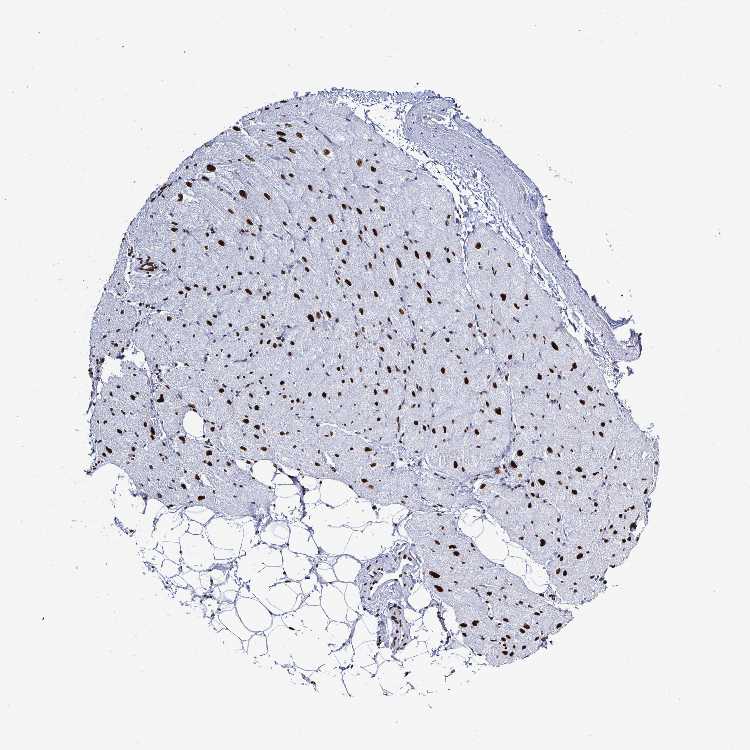

HEART MUSCLE - Antibody stainingi

Antibody staining in the annotated cell types in the current human tissue is reported as not detected, low, medium, or high, based on conventional immunohistochemistry profiling in selected tissues. This score is based on the combination of the staining intensity and fraction of stained cells.

Each image is clickable and will lead to virtual microscopy that enables deeper exploration of all samples and also displays staining intensity scores, fraction scores and subcellular localization as well as patient and tissue information for each sample.

Antibody HPA059098

Cardiomyocytes High